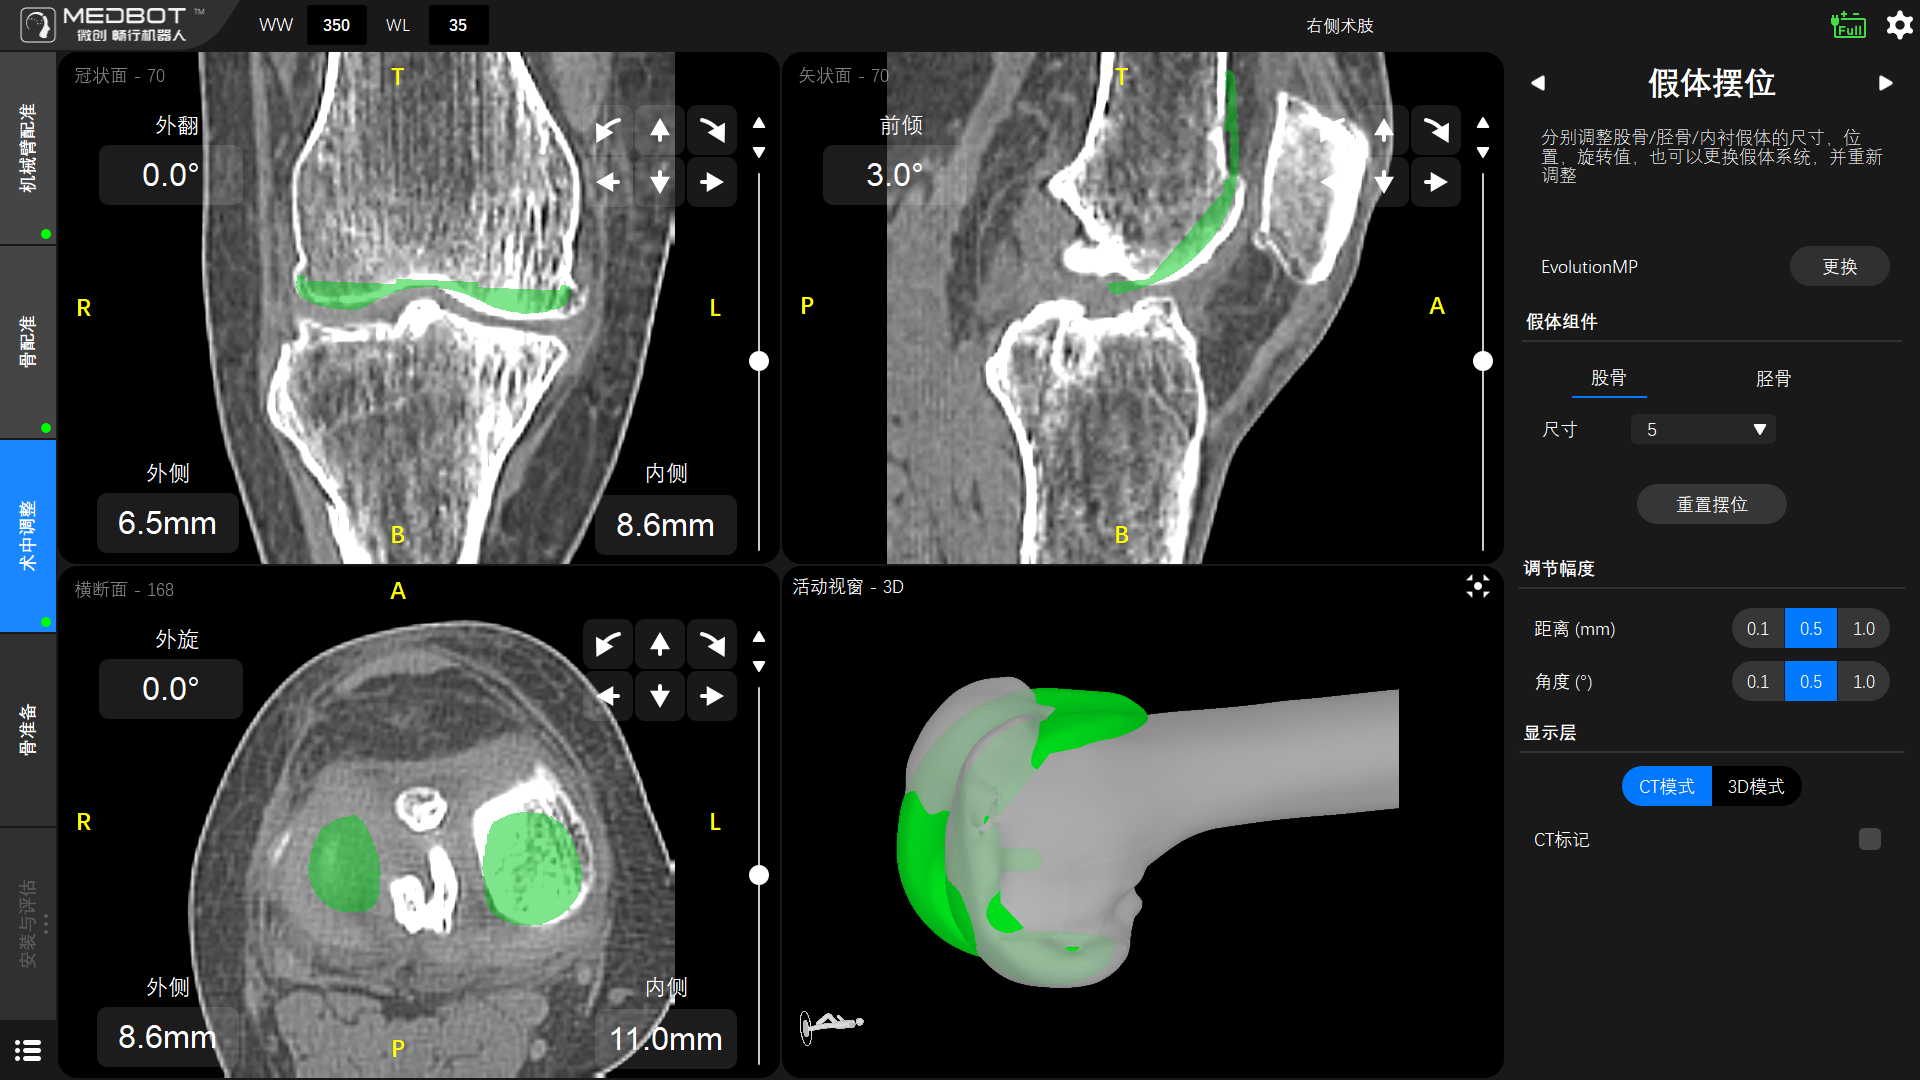

術(shù)前,薛勇主任和黎志超主任團(tuán)隊(duì)通過鴻鵠®機(jī)器人的規(guī)劃軟件為患者進(jìn)行了膝關(guān)節(jié)CT圖像的三維重建,制定符合患者生理解剖特征的個(gè)性化假體放置方案。

▲股骨假體擺位

▲脛骨假體擺位